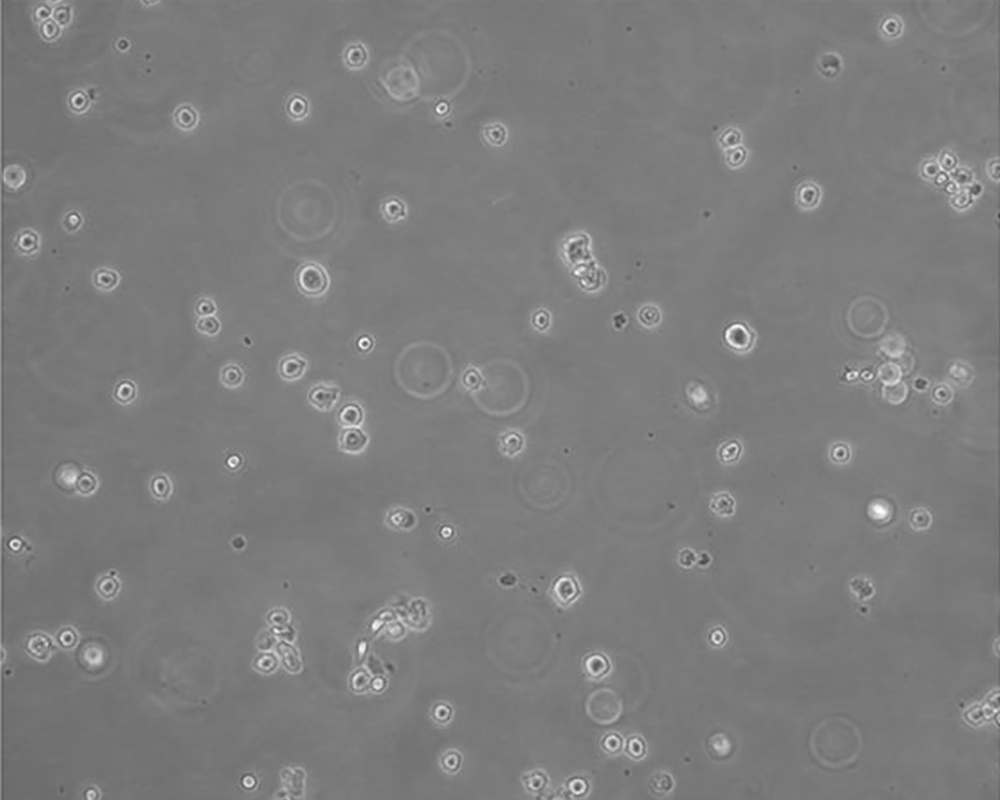

生長(zhǎng)特性 suspension

形態(tài)特征 lymphoblast

細(xì)胞描述 該細(xì)胞來(lái)源于多發(fā)性骨髓瘤男性患者,表達(dá)IgG,分泌IL-6。